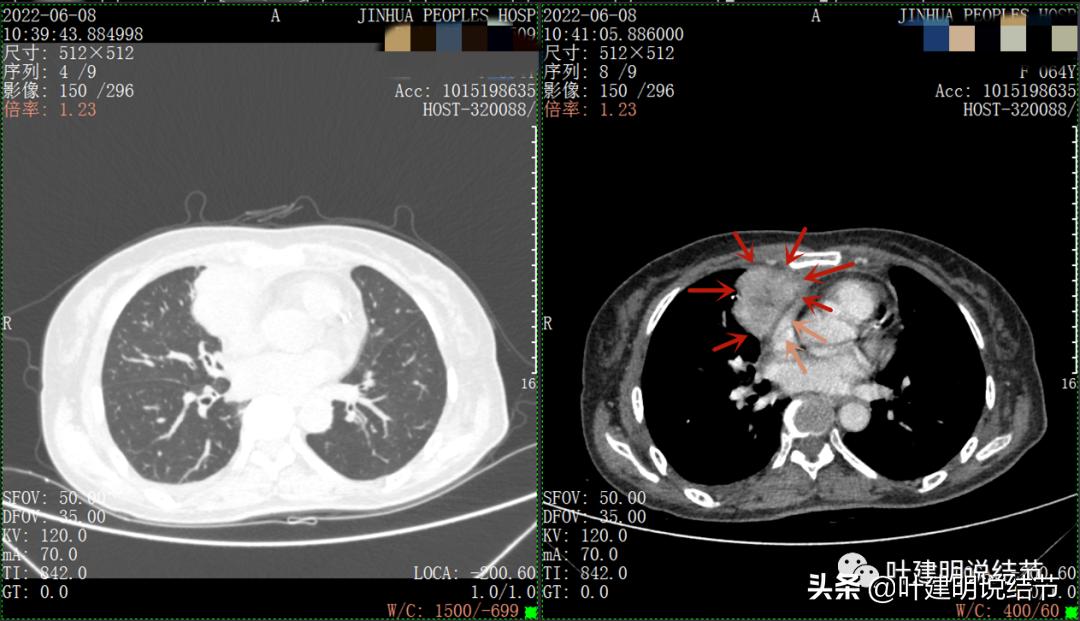

以下图片左侧是肺窗,右侧是纵隔窗。红色箭头示病灶,桔色箭头示无名静脉,黄色箭头示支气管,砖色箭头示上腔静脉,蓝色箭头示主动脉,紫色箭头示肺动脉。

绿色箭头示近膈面处,心脏边病灶

此灶与主病灶不是完全相连的

病灶占据前纵隔从上到下全程,多中心,密度不均,对心脏与大血管有压迫,没有明显侵犯

特别显示与无名静脉的关系